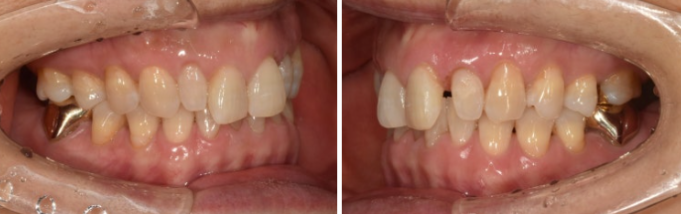

23.09~24.03

The alignment was well established.

Here is a comparison of the before-treatment and after-treatment photos, including Gelami.

23.09~24.08